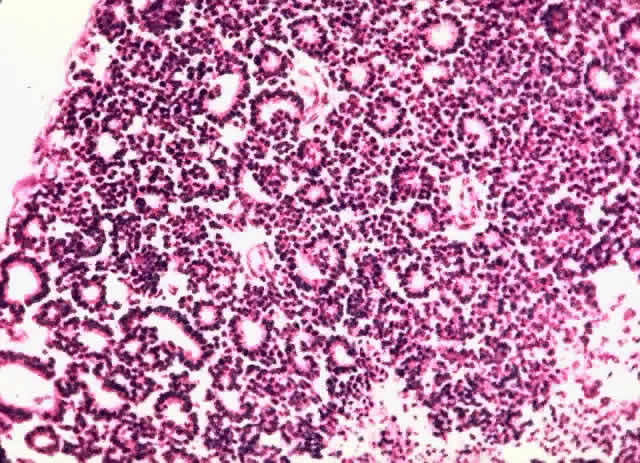

The cells tend to have large basophilic nuclei with little cytoplasm. Numerous mitoses and areas of necrosis with calcification are characteristic (Fig. 4). The rapidly growing tumor outstrips its blood supply. Cuffs of cells surround blood vessels. Viable cells may be found in the vitreous or subretinal space. Important pathologic findings affecting survival include extrascleral extension, choroidal invasion greater than 3 mm2, and optic nerve involvement.88

Fig. 4. Retinoblastoma (H & E, × 25)